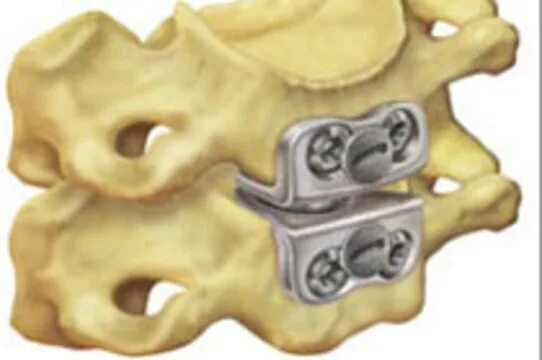

Установка кейджа в позвоночнике